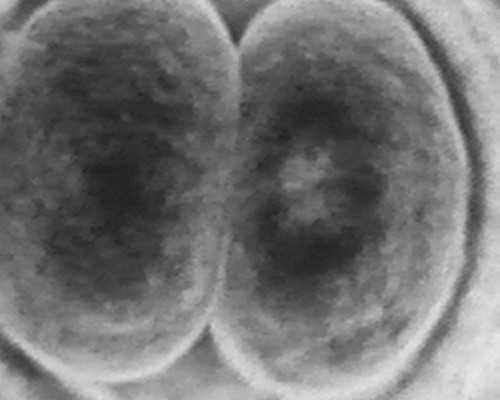

环节三:取卵、取精、培养受精卵

待卵泡成熟后,医生会在规定时间内给捐卵者注射绒毛膜促性腺激素,并在注射后的36小时内取卵。取卵当天,准爸爸也要到医院取精,待精子和卵子都取出后,医生就会对精子和卵子进行处理,并培养受精卵。